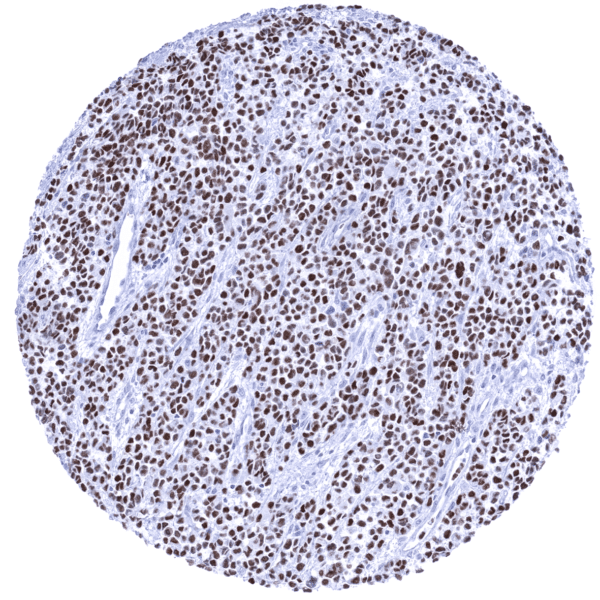

Positive control = Rhabdomyosarcoma with previously documented MyoD1 expression should demonstrate a moderate to strong nuclear MyoD1 immunostaining.

Positive control: Rhabdomyosarcoma with previously documented MyoD1 expression should demonstrate a moderate to strong nuclear MyoD1 immunostaining.

A positive MyoD1 immunostaining is seen in most cases of rhabdomyosarcoma. Rarely, a positive MyoD1 staining can also occur in various other tumor entities such as for example mesenchymal chondrosarcomas or sarcomatoid carcinomas.

Orthogonal validation: For the antibody MSVA-801R orthogonal validation by comparing the normal tissue immunostaining data with data from three independent RNA screening studies, including the Human Protein Atlas (HPA) RNA-seq tissue dataset, the FANTOM5 project, and the Genotype-Tissue Expression (GTEx) project, which are all summarized in the Human Protein Atlas (Tissue expression MyoD1) does result in concordant results. Immunostaining by using MSVA-801R is not seen in skeletal muscle (and tongue) as suggested by RNA expression data. This is not surprising, because of the low level of RNA expression which is unlikely to result in detectable protein expression. True detection of MyoD1 by MSVA-801R is suggested by the strong nuclear positivity seen in 3 of 4 analyzed rhabdomyosarcomas (images of all of these cases are shown in the tumor gallery). Non-nuclear MyoD1 immunostaining is sometimes seen for MSVA-801R in pancreatic acinar cells (granular cytoplasmic) and in mature placenta (membranous, superficial membrane of syncytiotrophoblast). These findings are considered a (tolerable) cross-reactivity.